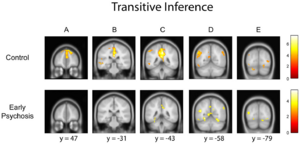

- 6.24 Intact Relational Memory and Normal Hippocampal Structure in the Early Stage of Psychosis